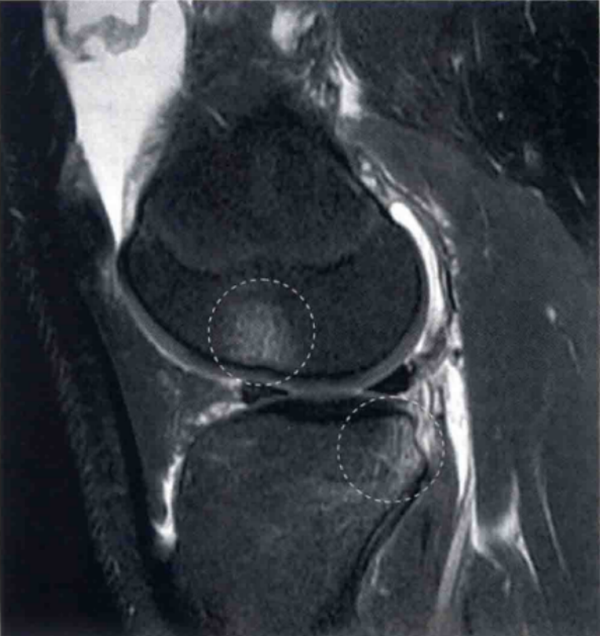

图2 a和b显示的为2个不同患者ACL损伤的表现。

a显示韧带呈波浪形,并且实质部中部不连续(圆形标记)。在b中直接可以看到ACL胫骨侧的残端(圆形标记)。标记了正常的PCL(白色箭头)